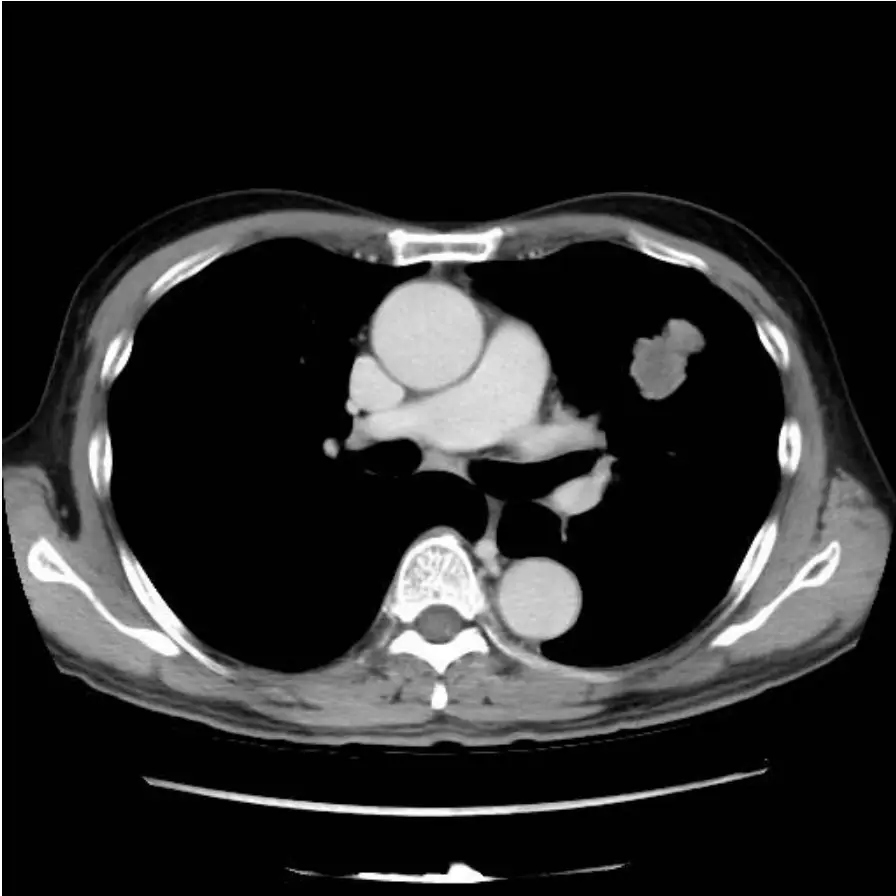

圖二(胸部電腦斷層,縱膈腔窗,較高層面): CT 橫切面呈現更上方的縱膈腔結構。右氣管前淋巴結(pre-tracheal / station 4R)更清楚可見,為一枚圓形軟組織結節,約 1 公分,位於氣管右前壁旁。左肺病灶在此層面仍隱約可見。兩側肺野其餘部分無明顯浸潤或結節。頭部 CT 及骨骼掃描已排除遠端轉移,本案為潛在可切除之 N2 疾病評估問題